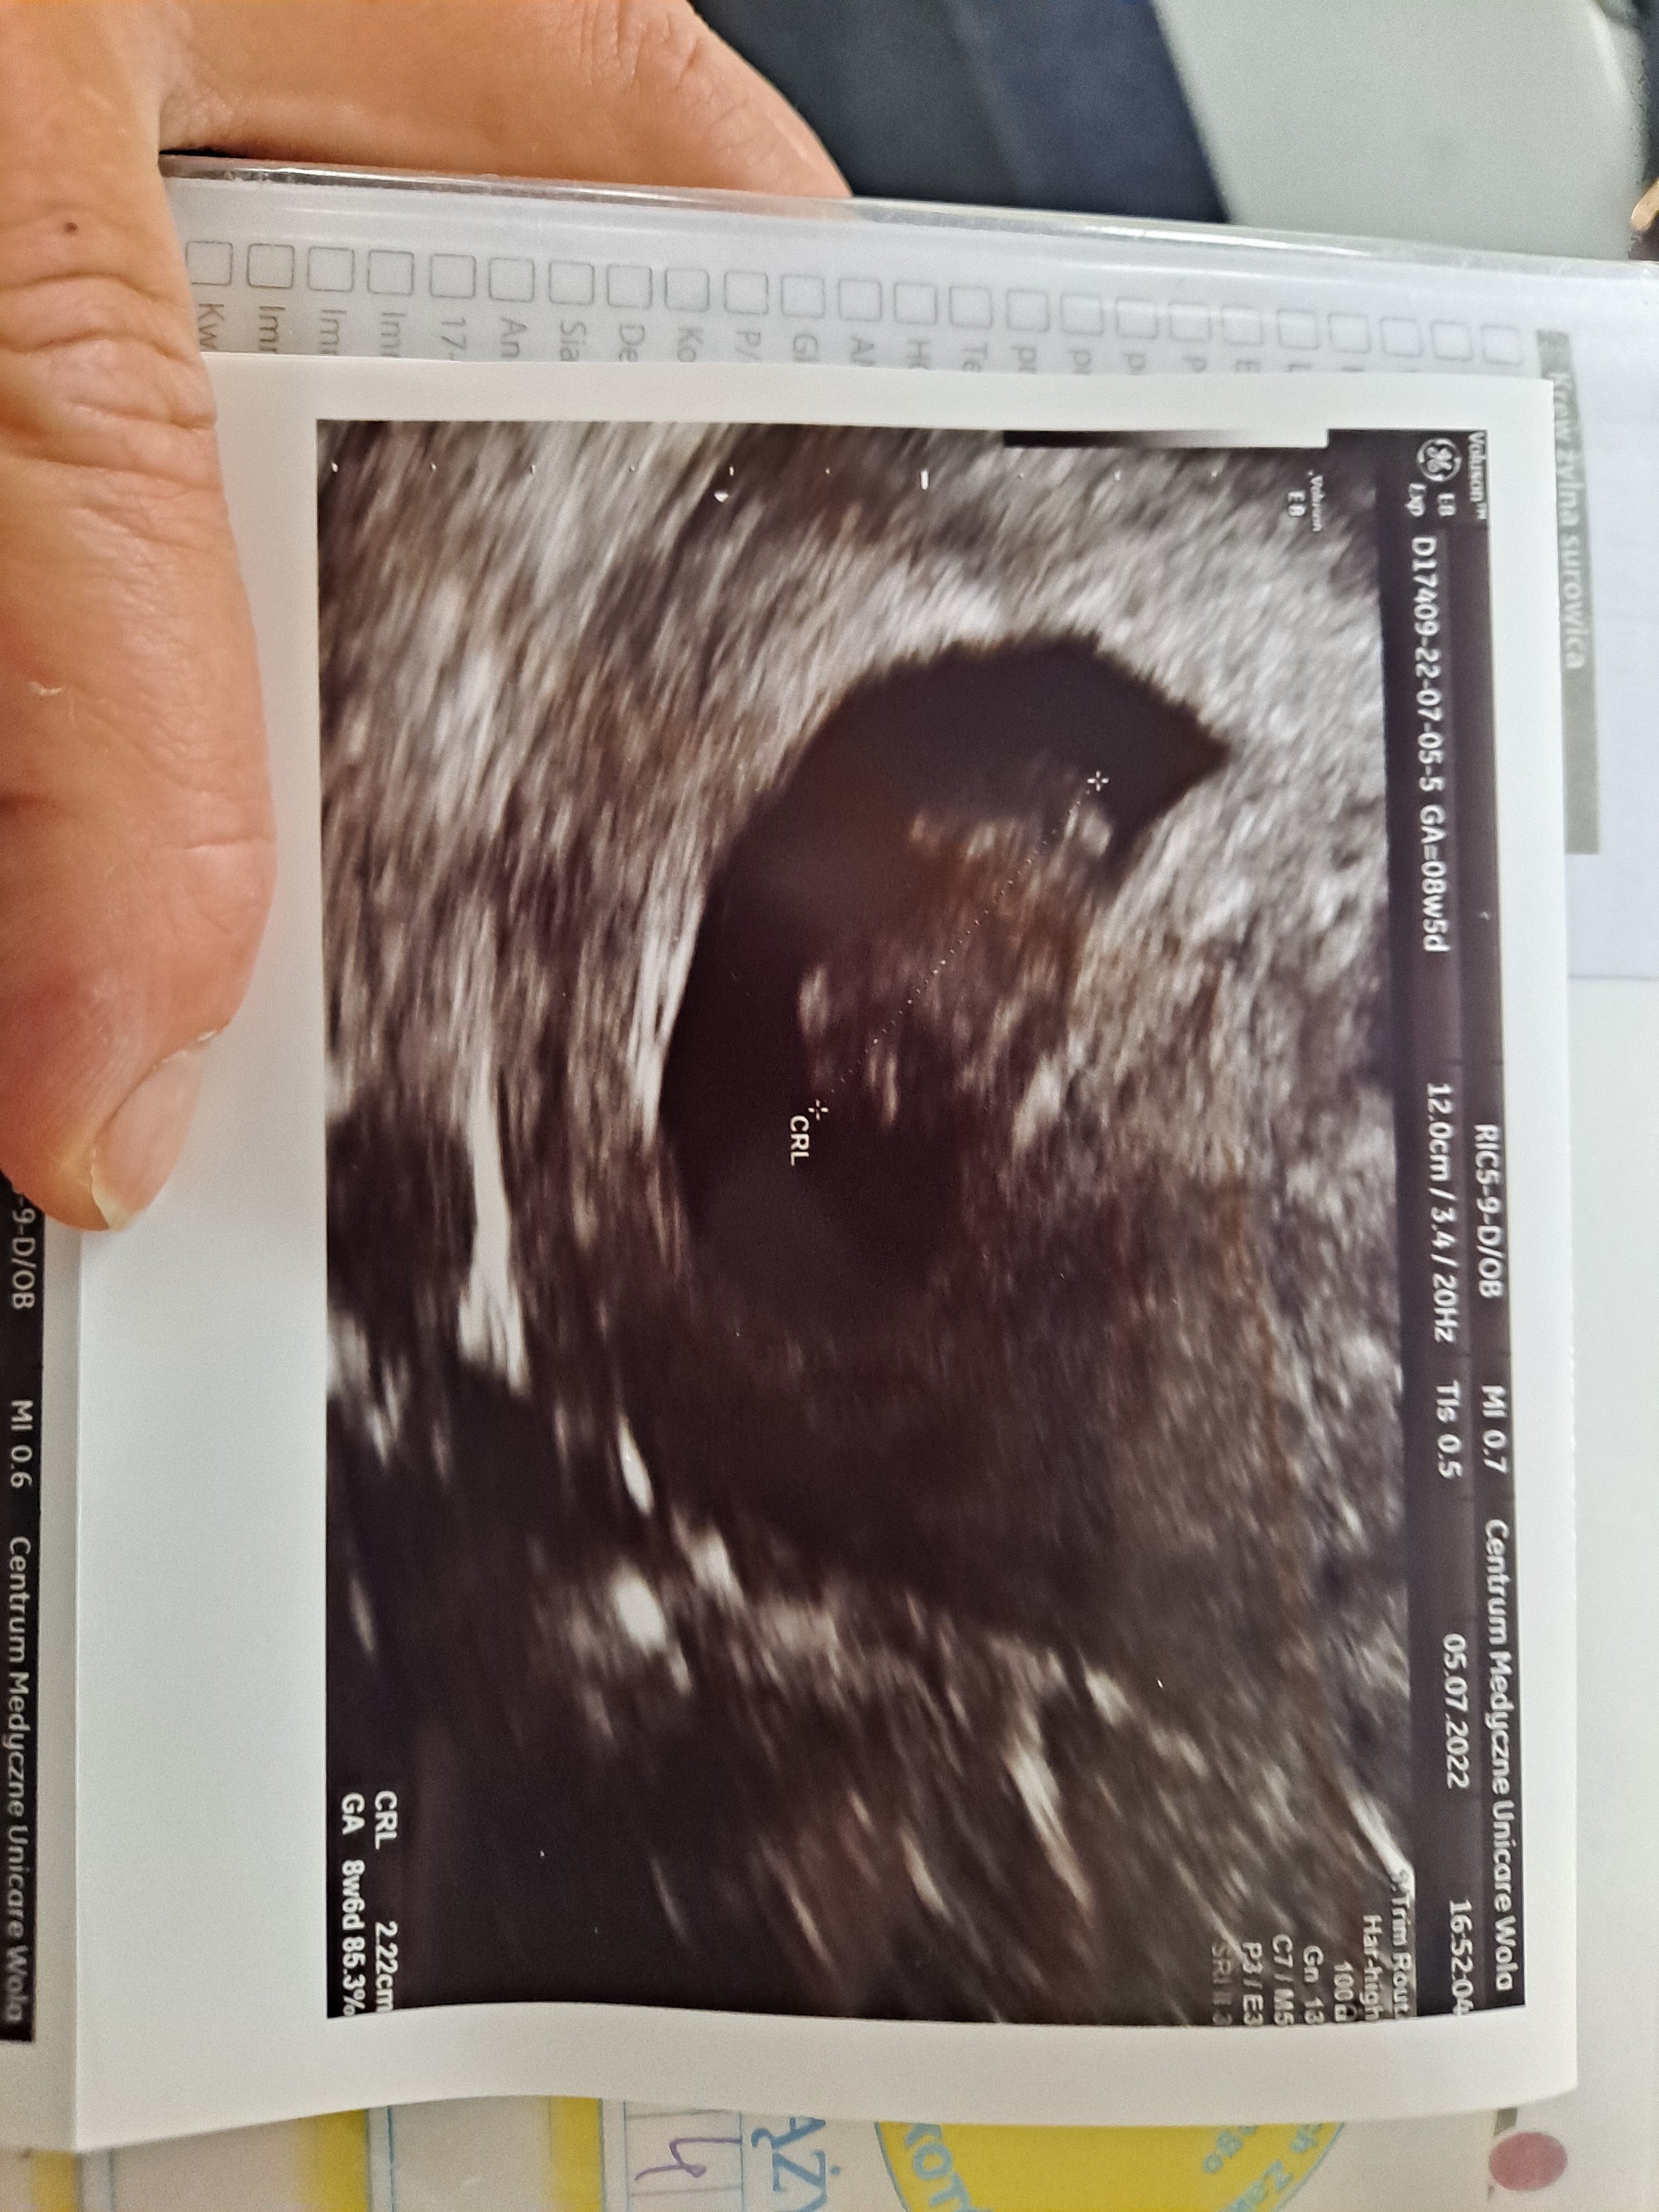

To ja się dzisiaj pochwalę zdjęciem z usg

Mdłości mi praktycznie odeszły, więc się zamartwiałam. Wg poprzedniego usg powinno być 7+2, a tutaj niespodzianka, 8+2 i serduszko bije

byłam u innego lekarza, z lepszym sprzętem. Mój prowadzący jest stary i ślepy i chyba jednak sprzęt ma słaby

teraz w końcu terminy mi się zgadzają, a nie ciąża młodsza z każdym usg

Ja po wizycie

Wszystko jest idealne jak to powiedział mój doktor.

Zbadał i na fotelu i zrobił usg.

Mój groszek mierzy 2,22mm

bije jak szalone 160 uderzeń

Obecnie mamy 8+5 tc

Termin na 9.02.2023

Jestem spokojna i szczęśliwa

ROŚNIJ MÓJ GROSZKU